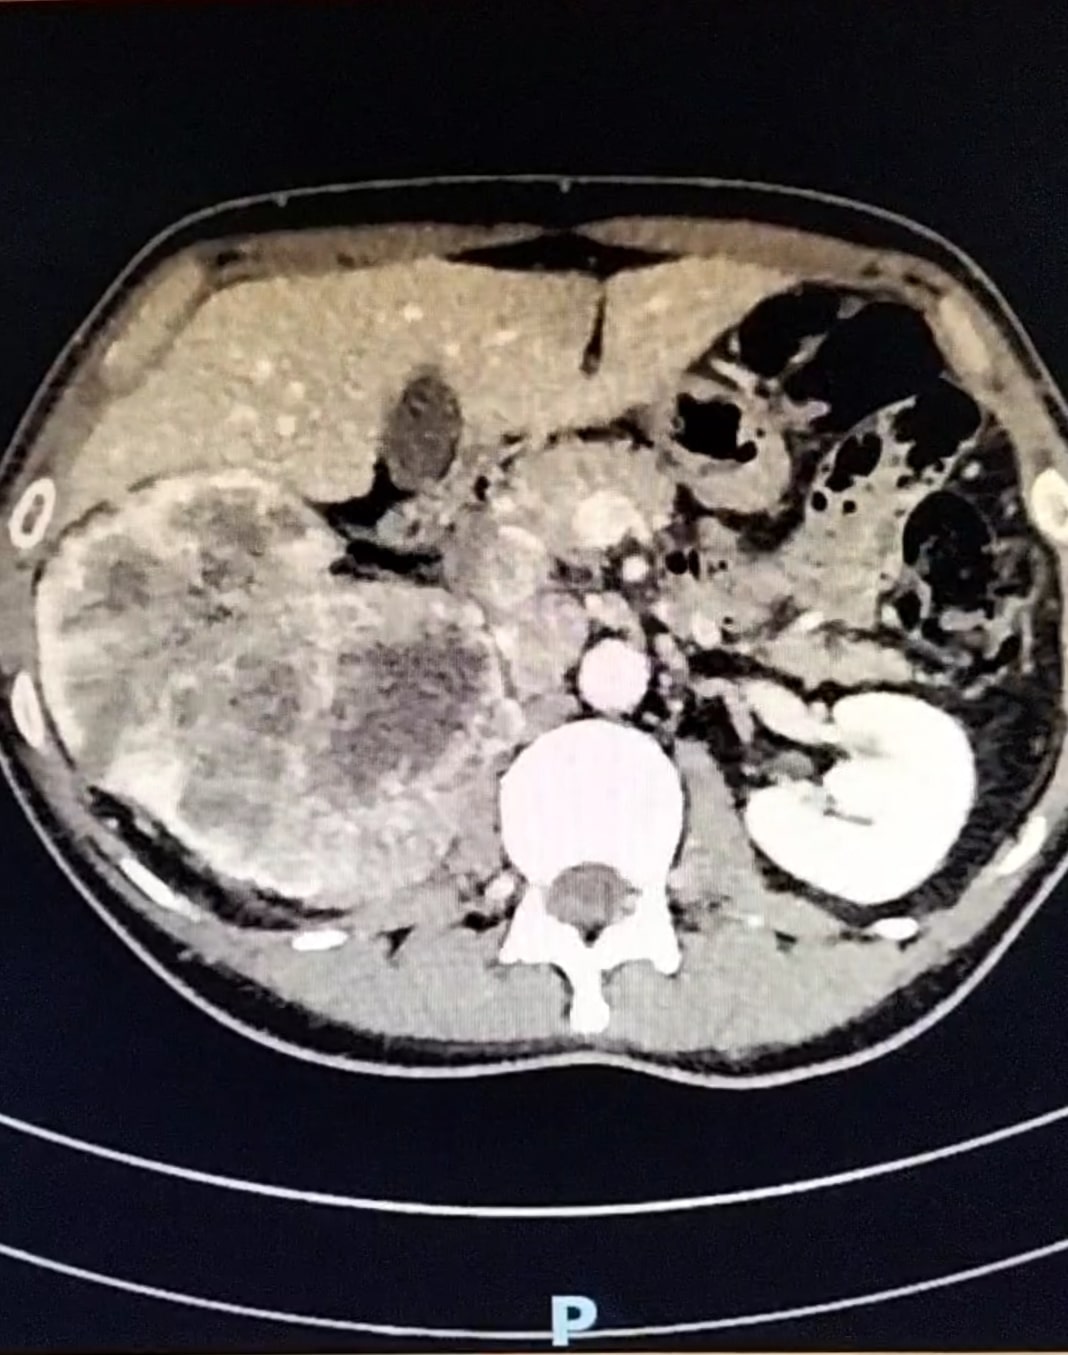

En la analítica sanguínea se destaca deterioro de la función renal y la analítica de orina señala la presencia de hematuria. Se comenta el paciente con el Servicio de Radiología y se consensúa realización de TAC tóraco-abdominal, donde se objetiva una neoplasia renal derecha que infiltra arteria y venas principales, con trombosis de la cava desde el hilio renal hasta la porción intrahepática así como adenopatías retroperitoneales.

Neoplasia renal derecha.